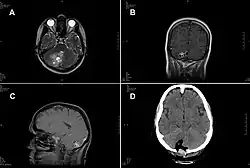

Cranial MRI of the German woman as described. A- Transverse view, T1-weighted MR image. The 30 × 30 mm parasitic lesion with perifocal edema is located in the right hemisphere of the cerebellum and caused ataxia, headache, and nausea. The fourth ventricle is compressed. B- Coronal view, T2-weighted MR image. The cyst-like appearance of the parasitic tissue is clearly visible. This lesion can be misinterpreted as cerebral echinococcosis, racemose cysticercosis caused by a Taenia solium tapeworm, or coenurosis. C- Sagittal view, MR image with contrast enhancing agent. D- Transverse view, computed tomographic image after surgery.

A case of intracranial T. crassiceps tapeworm cysticercosis with severe involvement of the cerebellum is described. A 51-year-old German woman was hospitalized because of progressive headache, nausea, and vomiting. The signs and symptoms had started two weeks before, and intensity had been increasing ever since. At the time of admission, the patient showed cerebellar ataxia but no further neurologic deficits. She did not have fever or other symptoms. She had no known chronic preconditions or recent hospital stays and had never taken immunosuppressant drugs. She had no family history of neurologic symptoms or malignant diseases. Combined surgical removal of the larvae and treatment with albendazole and praziquantel led to a complete cure in this nonimmunocompromised patient. The organism was unequivocally identified by molecular methods, thus avoiding a misdiagnosis of Taenia solium tapeworm cysticercosis.[5]